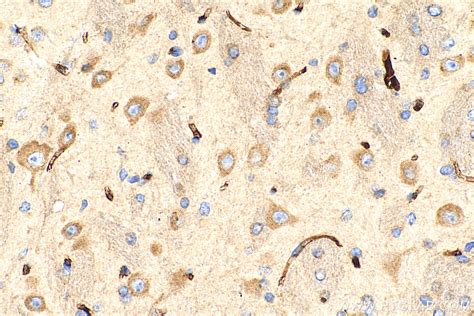

MIA3 antibody (17481-1-AP) | Proteintech